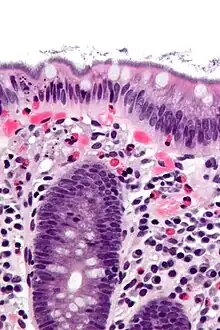

| Histopathology of intestinal spirochetosis, showing basophilic, fringe-like, end-on-end attachment of filamentous densely packed spirochetes on the surface epithelium of the intestinal mucosa.[1] H&E stain. | |

Human intestinal spirochetosis, often called just intestinal spirochetosis when the human context is implicit, is an infection of the colonic-type mucosa with certain species of spirochetal bacteria. Similar infections sometimes occur in pigs, dogs, and birds; porcine intestinal spirochaetosis is an economically important disease of livestock.

Human intestinal spirochetosis is caused by Brachyspira pilosicoli and Brachyspira aalborgi.[3] Porcine and avian intestinal spirochetosis are caused by Brachyspira hyodysenteriae and Brachyspira pilosicoli.